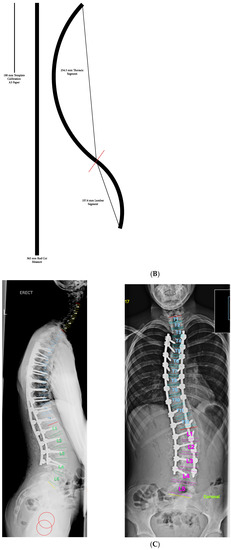

2. Materials and Methods

3. Results

3.2. Sagittal Plane Correction Parameters

3.3. Comparison of TK Achieved with Templating